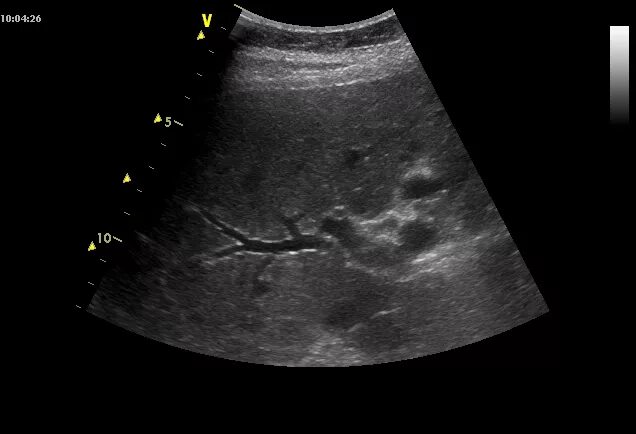

Расширен проток